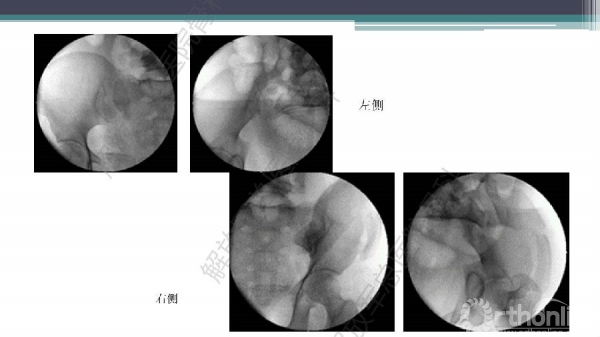

随着建筑和交通运输业的快速发展,合并骨盆、髋臼骨折多发伤、复合伤患者逐年增加,病死率和致残率都非常高。由于多发伤及复合伤、休克等往往不能在急性期对骨盆骨折进行确切复位及内固定,导致陈旧性骨盆骨折畸形愈合,从而产生一系列严重并发症,并且畸形矫正手术难度大、风险高、效果差。因此在抢救复苏后能不能尽早地、小切口甚至不切开、精确复位与固定骨盆骨折,防止陈旧性骨盆畸形愈合形成,成为广大骨科医生的挑战。解放军总医院创伤骨科在骨盆、髋臼骨折微创治疗方面做了一些工作,从微创理论探讨、到手术方法的改进,乃至钢板螺钉、微创复位器械等相继研发,形成了一系列的解决方案和配套内固定产品,为骨盆髋臼骨折的微创治疗奠定了基础。本幻灯则通过一例陈旧骨盆骨折畸形愈合的复杂治疗做引,通过介绍骨盆空间移位方式、透视特点、骨盆随意外架复位系统、复位原理以及1例典型病例的具体实施方案来综合、全面介绍我院微创骨盆髋臼骨折复位、固定新技术。